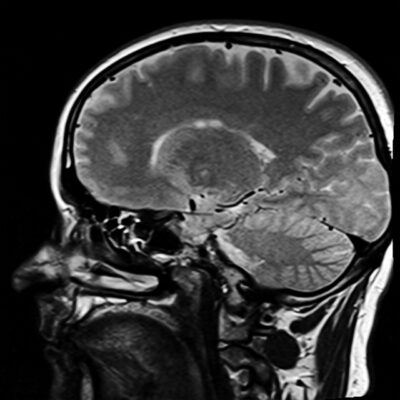

According to the Cleveland Clinic, “Normal pressure hydrocephalus (NPH) is a brain condition that happens when [cerebrospinal] fluid buildup inside or around your brain disrupts your brain function. That can affect several brain-related abilities, including thinking and concentrating, memory, movement and more.”

According to the Hydrocephalus Association, an estimated 800,000 Americans have NPH, but only around 20% are diagnosed properly. NPH is often misdiagnosed as Alzheimer’s or Parkinson’s disease. Common symptoms include awkward gait, dementia, and urinary incontinence (also referred to as “wet, wacky, and wobbly”). There can be other symptoms, too.

If the CS fluid is continually added around the brain tissue without a similar amount of draining, pressure builds up on the brain. Too much pressure can result in pathological symptoms such as those found in NPH and other forms of hydrocephalus.

This study noted that CS fluid can build up around the brain due to a variety of reasons, in particular “due to obstruction and fibrosis of subarachnoid villi.” This is the fascial tissue around the brain that helps drain the used CS fluid and its wastes and helps get it to the venous system for eventual elimination from the body.

In other words, this tissue can also dehydrate, glue together, and harden into fascial adhesions, just like dysfunctional tissue anywhere in the body. The consequence is that those waste products from the CNS are not leaving the area around brain and spinal cord properly, and harmful pressure is continually building on the brain cells.

The study also notes that, while a shunt is often a very successful treatment, “nearly 16% of shunts in adults fail over six years…Only a fraction of patients with NPH receive shunt surgery, and only 60%-80% improve following shunt surgery…Furthermore, complications include mechanical malfunctions on the shunt, blockages, and infections.”